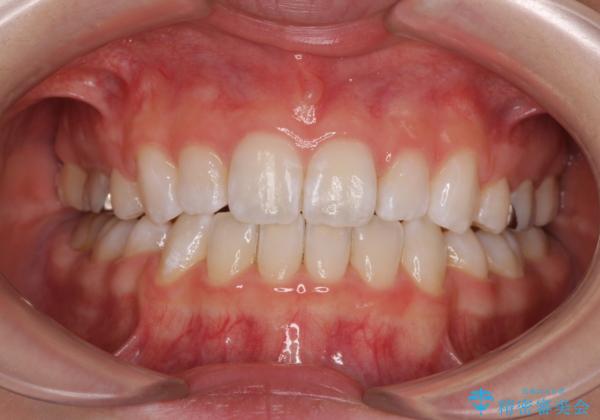

- 前歯の出っ歯と口元の閉じにくさを気にして来院された患者様です。

口元を積極的に引っ込めるために、上下左右の小臼歯4本を抜歯することとしました。

4本の歯を抜歯したことで、飛び出していた口元が引っ込み、横顔が大きく改善されました。